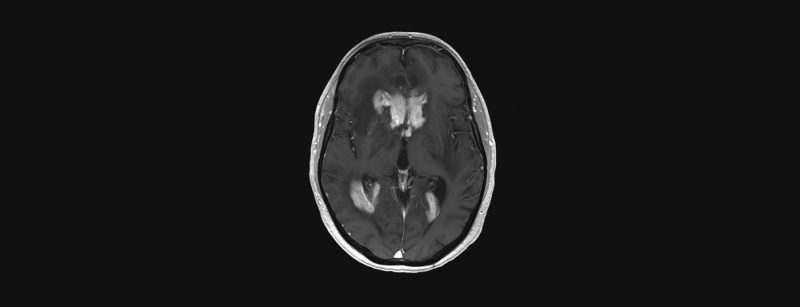

Erweiterte MRI-Diagnostik (Spektroskopie, DWI, PWI) und MRI-gestützte Biopsie

Einleitung: Primäre ZNS-Lymphome, überwiegend vom B-Zell-Typ, sind seltene Tumore mit einem Häufigkeitsgipfel im mittleren bis höheren Lebensalter. Die konventionelle MRT-Untersuchung liefert im Wesentlichen unspezifische Befunde einer zumeist KM-aufnehmenden, typischerweise Ventrikel-nahen...…